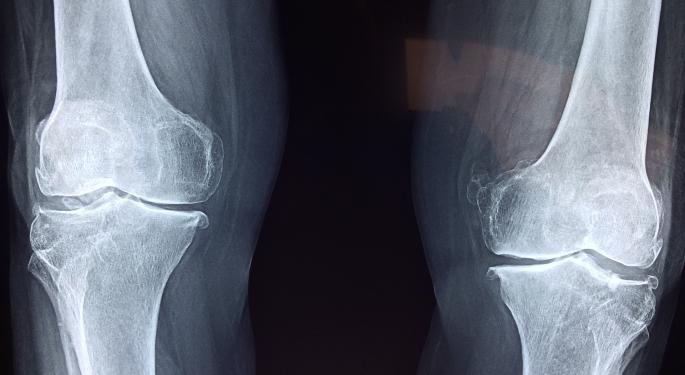

PF708 has been indicated to treat osteoporosis in certain patients at high risk for fracture.